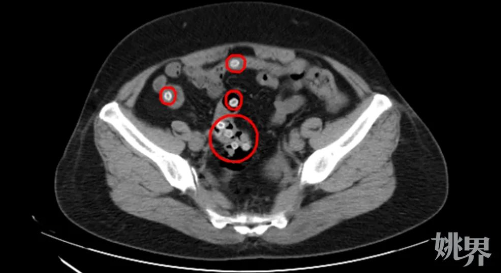

CT影像顯示,患者腸道內有不少楊梅核滯留

CT影像顯示,王阿姨的腸內存在多處類圓形高密度影,密密麻麻的圓圓小白點正是滯留在腸道內的楊梅核,這是導致患者腹痛不止的罪魁禍首。“這種情況下,患者很有可能會引發(fā)胃痙攣和腸梗阻,要盡快將楊梅核排出體外?!惫燃t蘋首先為患者進行解痙止痛治療,然后為其開具了通便的藥物促楊梅核排出。在藥物的幫助下,王阿姨成功在第二天完成排便,腸道內的楊梅核也順利排出體外。谷紅蘋表示,楊梅核本身非常堅硬,很難被腸胃消化,特別是老人和嬰幼兒要更加當心,吞食楊梅核還可能誤入氣道,引發(fā)窒息風險。如果是無意間吞咽下一兩顆楊梅核,對于人體來說并無大礙??扇绻锹犘潘酥{傳,刻意吞咽大量楊梅核,不僅容易噎住,還會在狹窄的腸道內產生淤堵引起腹痛癥狀,甚至可能引發(fā)胃出血、腸穿孔或是腸梗阻等多類腸胃疾病,后果不堪設想。“從中醫(yī)角度來看,從未有過吞食楊梅核治病的說法。”谷紅蘋說,她查閱相關文獻,只有記載將楊梅核碾碎成粉末,煎煮后泡腳,有一定治療腳氣的功效。吃楊梅核可以排毒清腸只是謠傳。谷紅蘋提醒廣大市民,胃潰瘍、十二腸潰瘍、消化道炎癥、慢性便秘和有過消化道手術病史的人群,絕對不可吞食楊梅核,這樣極易引發(fā)腸梗阻、胃腸穿孔等疾病,嚴重時可能會威脅生命,風險不容小覷!根據(jù)《中國居民膳食指南》建議,水果每天攝入量最好控制在200~350g,如果一天水果類只吃楊梅,食用量建議不超過20顆。食用楊梅后應及時漱口或刷牙,以免損壞牙齒。胃病患者:有胃炎、胃潰瘍的患者,盡量控制吃楊梅量。胃酸大量分泌,大量的消化液充盈在胃部,反復刺激消化性潰瘍炎癥部位,容易出現(xiàn)潰瘍出血,進而引發(fā)劇烈胃痛等胃部不適。糖尿病患者:楊梅的含糖量在10%以下,屬于含糖量較低的水果,“糖友”可以選擇食用。但并不是所有的糖尿病患者都可以吃楊梅。血糖不穩(wěn)定的患者,在高血糖的基礎上再攝入楊梅,會導致血糖進一步升高。腎功能不全患者:楊梅含鉀量高,100g楊梅中的含鉀量就有149mg。而我們人體中80%-90%的鉀由腎臟排出,對于腎功能不好的人來說,腎臟無法排出過量的鉀,就會非常危險,應特別注意避免過量食用。來源:寧波晚報、寧波疾控